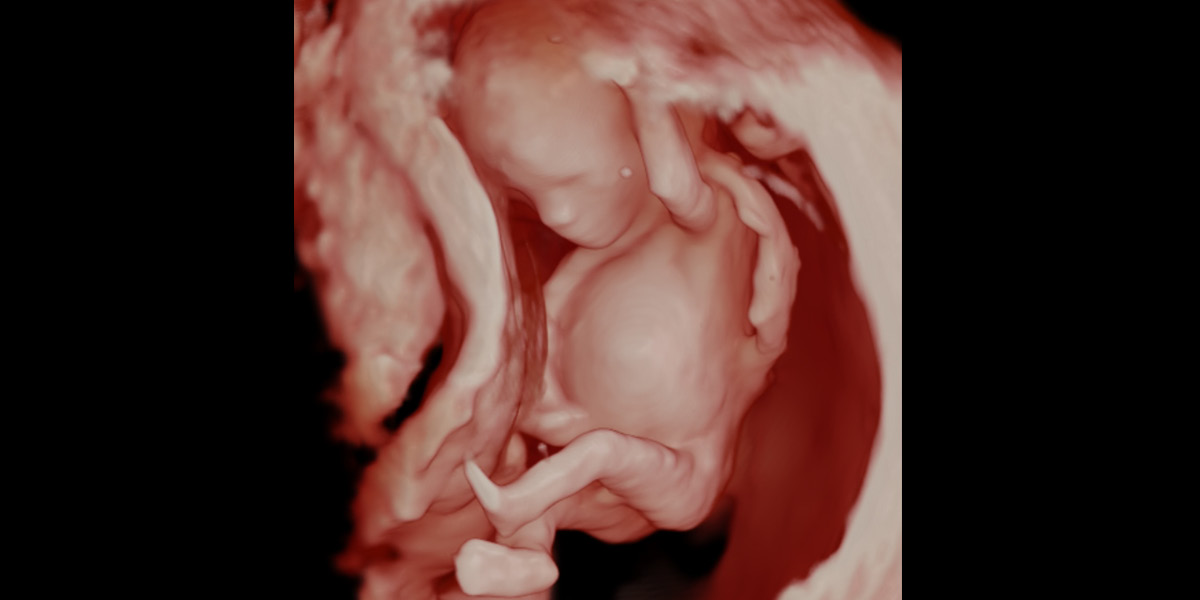

Bei besonders guten Untersuchungsbedingungen können auch 3D/4D-Aufnahmen entstehen.